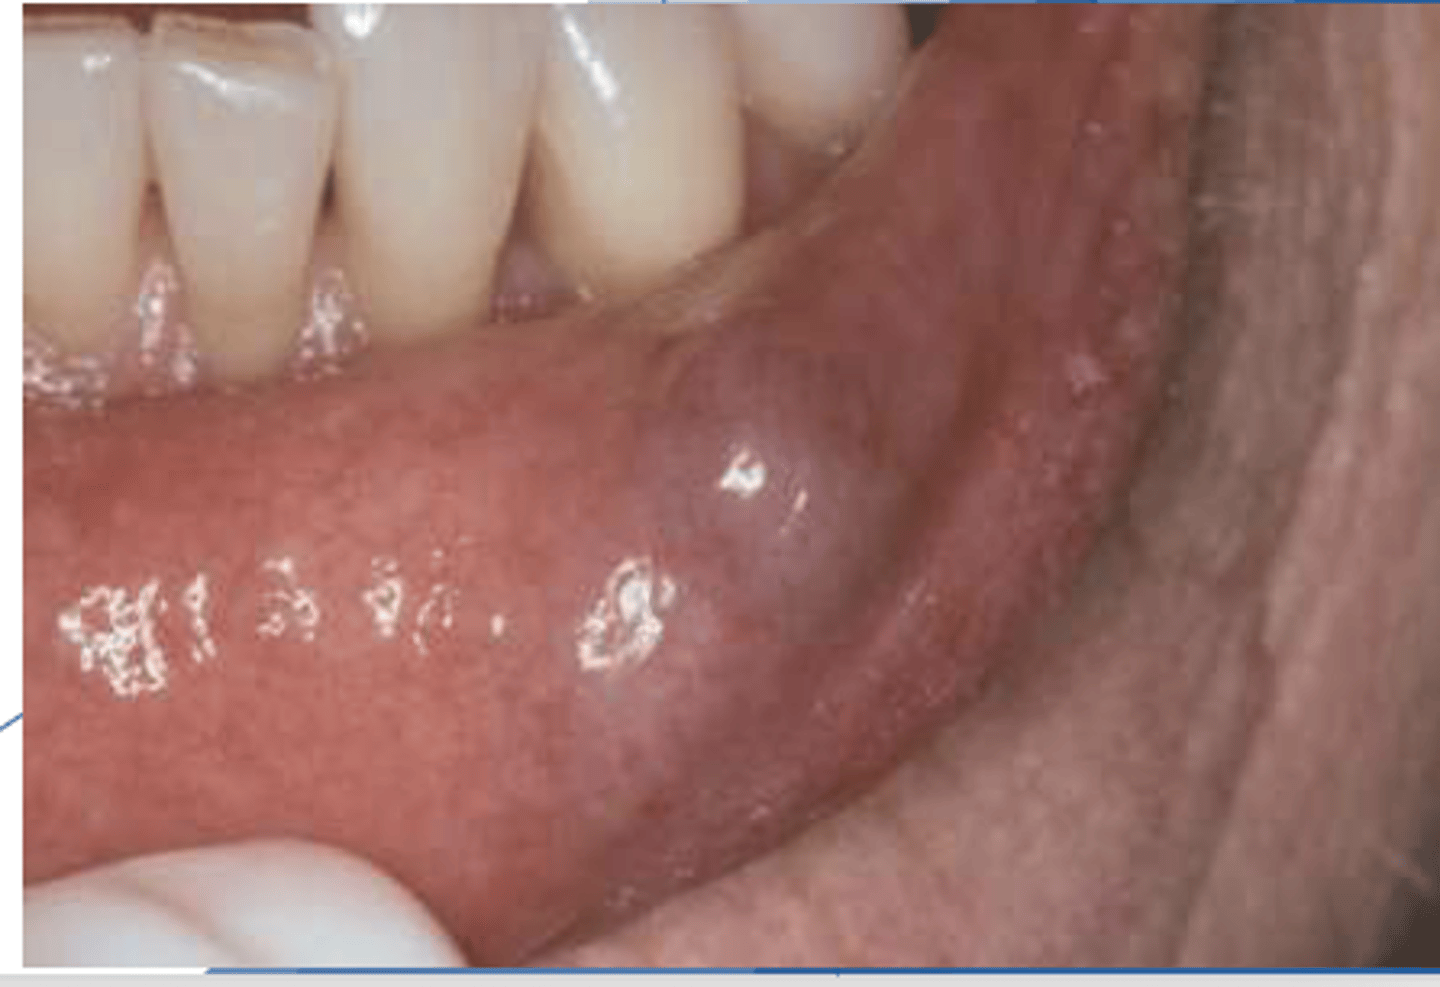

ID the pathology:

- Common reactive salivary gland lesion

- - Traumatized duct spills mucus into adjacent tissues

- Characteristic hx of increasing/decreasing in size

Mucocele

These are clinical features of what pathology?

- Dome-shaped fluctuant vesicle

- Blue or mucosa-colored

- Most common on lower lip

- - May be seen anywhere w/ salivary glands